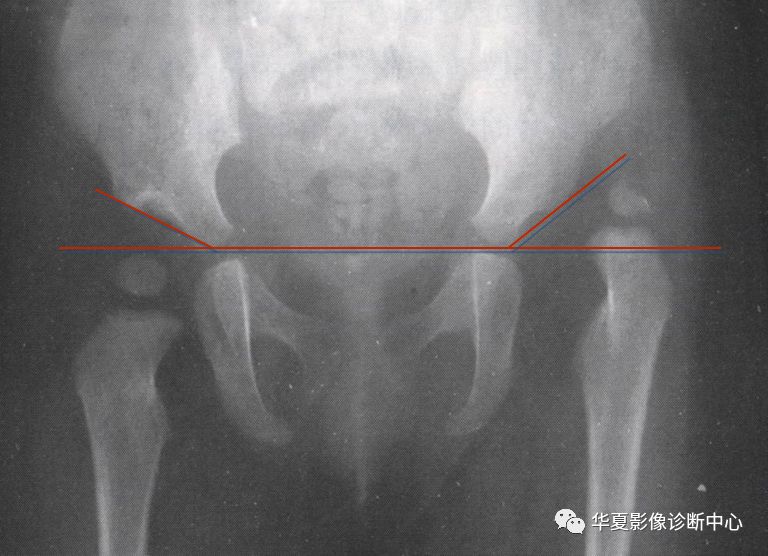

1.Von-Rosen (外展内旋位)摄片法

婴儿仰卧位,双下肢外展45度,尽力内旋位摄片。

正常时骨干轴线向上的延长线经髋臼外缘相交于腰5与骶1的平面以下。但脱位时此线经髂前上棘相交于腰5骶1平面以上。